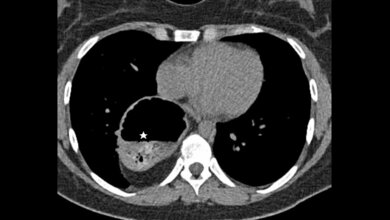

Die pulmonale arteriovenöse Malformation ist eine abnormale Verbindung zwischen einer Pulmonalarterie und Pulmonalvene. Die endovaskuläre Behandlung der den Nidus versorgenden Arterie mit Embolisation oder der drainierenden Vene hat sich zur Therapie der Wahl entwickelt, bedingt durch die Entwicklung der interventionellen Materialien.

Pulmonary arteriovenous malformation is an abnormal communication between the pulmonary artery and pulmonary vein without an intervening capillary communication. Endovascular treatment, that is, selective embolization of the pulmonary artery feeding the nidus of the pulmonary AVM, and/or selectively either the nidus or draining vein, has become a first-line treatment with advances in interventional devices.